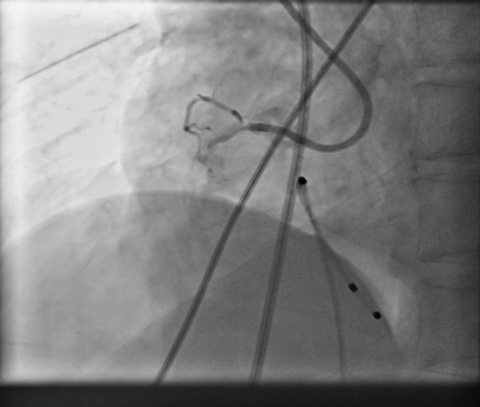

PCIof right coronary artery was initiated on IABP support with amplatz left1 guided catheter and vessel was crossed with great difficulty in repeatedattempts by fielder XT followed by GAIA 2 wire over corsair microcatheter. Microcathetercould not be crossed beyond mid segment calcified CTO, so balloon dilation with0.75 mm balloon was done after which again microcatheter could not be trackedbeyond mid part. Butwe were able to exchange wire to allstar followed by rotawire byplacing microcatheter in mid segment after balloon dilation by 0.75 mm balloon. Rotablation wasdone with 1.25 mm burr at 1,60,00 rpm repeatedly from proximal to mid distalpart. Lesionstill looked unprepared as repeated postdilation with2.25*15 mm followed by 2.5*15 mm non compliant balloon at high pressures showedunexpanded balloon. Againlesion preparation was done with 2.5*15 mm wolverine cutting balloon repeatedlyat high pressures which led to adequate luminal gain and calcium cracks as seenon IVUS run. AfterIVUS run again high pressure balloon dilation was done with wolverine 2.5*15 mmballoon followed by 2.5*12 mm non compliant balloon at 28 atm toadequately prepare the lesion before stent deployment. Stentingwas done with 2.5*32 mm DES, 2.75*32 mm DES, and 3*24 mm DES from distal toproximal in overlapping fashion. Thenfinally high pressure post dilation was done with 2.75*15 mm followed by 3*15mm non compliant balloon and adequate stent expansion was achieved with TIMI 3 flow.